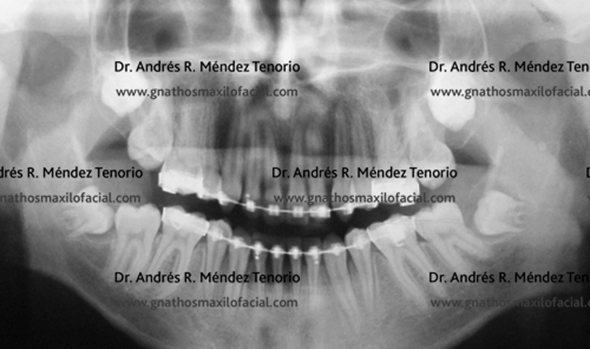

| Radiografía panorámica de un paciente con retención de 3os molares en múltiples posiciones. |